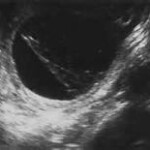

Στὴν τελευταῖα, κύτταρα τοῦ ἐσωτερικοῦ τοιχώματος τῆς μήτρας μεταναστεύουν σὲ ἄλλες θέσεις τοῦ σώματος (ὠοθῆκες, σάλπιγγες, ἔντερο, στὶς χειρουργικὲς (ἀπὸ καισαρικὴ τομὴ) οὐλὲς τοῦ δέρματος, στὸ στομάχι κ.ἄ. Συνεπῶς ἐδῶ μπορεῖ νὰ ἔχουμε συμπτώματα καὶ ἀπὸ ἄλλα σημεῖα τοῦ σώματος. Στὴν ἐνδομητρίωση συχνὲς εἶναι οἱ κύστεις ἐνδομητριώσεως, ποὺ μποροῦν νὰ ὁδηγήσουν τὴν γυναῖκα ἀκόμη καὶ στὸ χειρουργεῖο. Ἡ διάγνωση τίθεται ἐκ τοῦ ἱστορικοῦ, τῆς κλινικῆς ἐξετάσεως ὑπὸ τοῦ γυναικολόγου καὶ τοῦ διακολπικοῦ ὑπερηχογραφήματος ἔσω γεννητικῶν ὀργάνων.